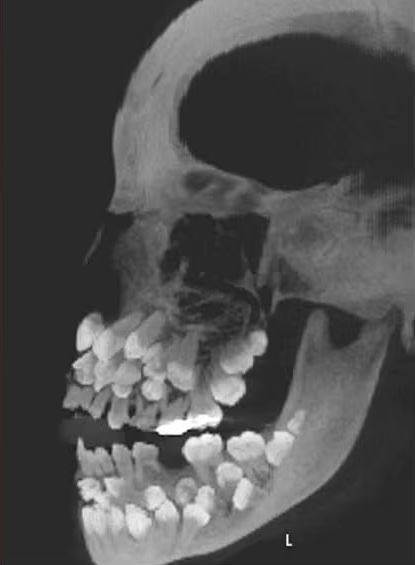

一名11歲的巴西女童因乳牙搖搖欲墜,到牙科診所看診,怎料醫生在拍完X光後,發現她嘴裡竟塞了81顆牙齒!

根據媒體《Chosun Biz》的報導,《美國齒顎矯正與顏面矯形學期刊》2011年曾刊登一起罕見病例,巴西一名11歲女童因想拔除一顆上排乳牙就醫,起初牙醫進行口腔檢查時並無異狀,誰知在照完X光後醫生大驚失色,因為女童嘴裡竟藏了18顆乳牙、32顆恆牙,以及31顆多生牙,一張小嘴共擁有多達81顆牙齒。